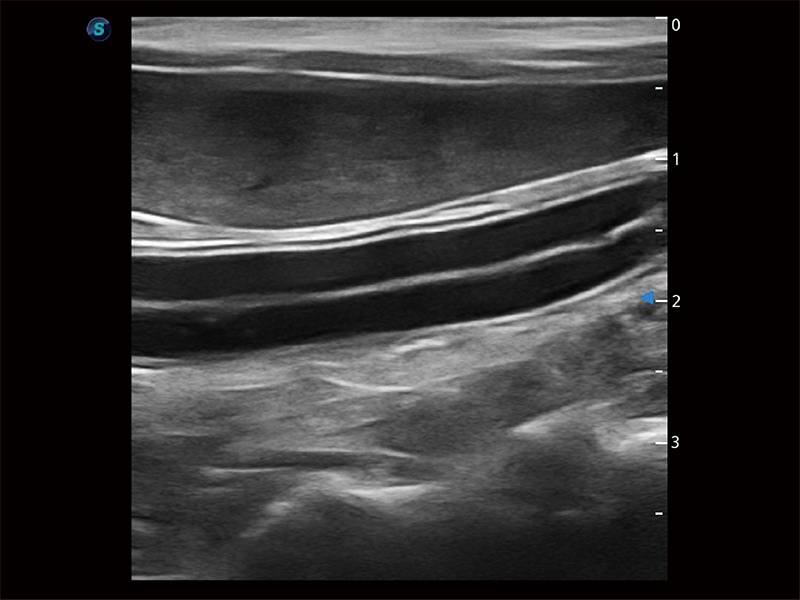

高性能和先进的临床应用工具可以为动物医生提供临床信心。ProPet 80 搭载了先进的腹部和浅表应用工具,帮助医生在日常临床实践中发挥前所未有的作用。

为精细结构及组织边缘提供高清晰度的图像和更大的成像视野。帮助减轻医生的用眼疲劳,快速精准获得测量的数据。